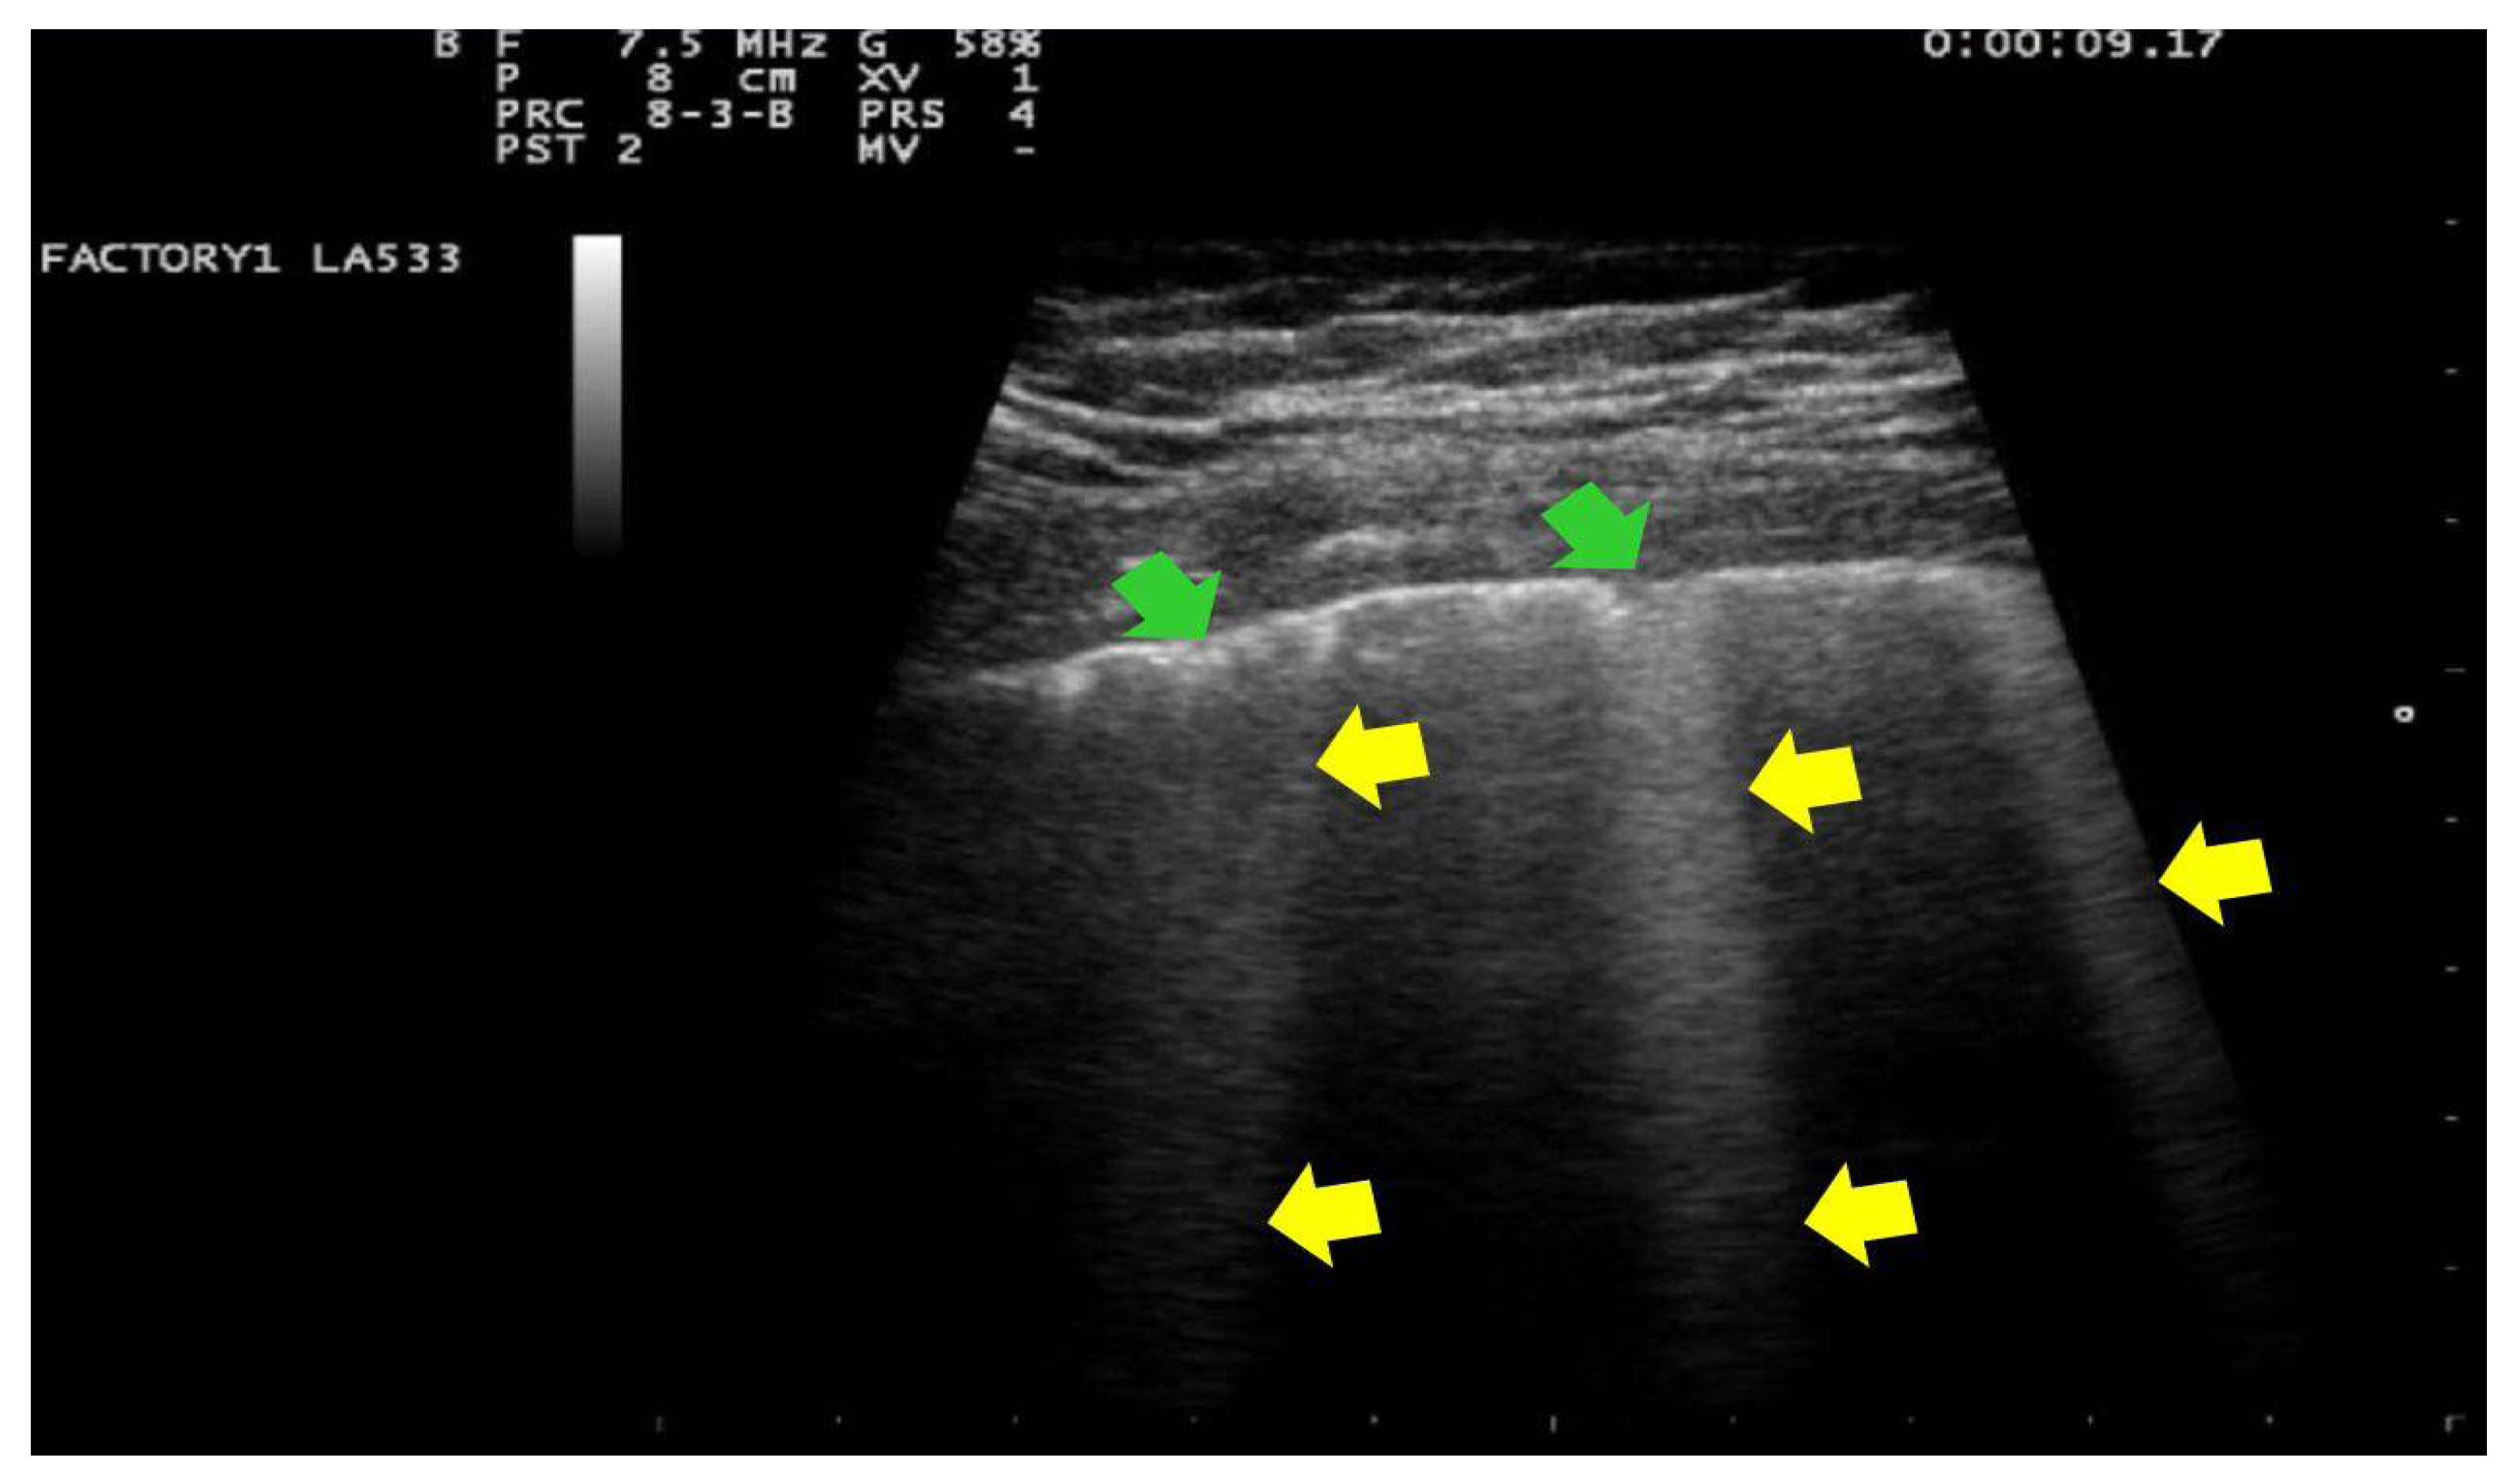

- Score 3:

- consolidations of large dimensions (at least >1 cm). (Figure 4)